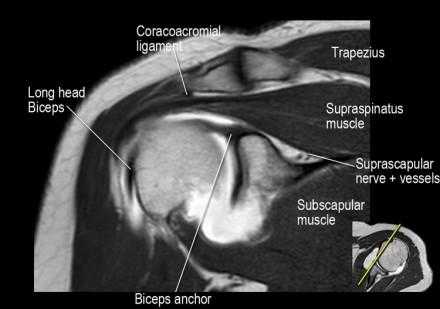

Нормальная корональная анатомия плечевого сустава и контрольный список

- обратите внимание на клюво-ключичную связку (coracoclavicular ligament) и короткую головку двуглавой мышцы (short head of the biceps).

- обратите внимание на клювоакромиальную связку (coracoacromial ligament).

- -

- обратите внимание на надлопаточный нерв и сосуды (suprascapular nerve and vessels)

- поищите импинджмент надостной мышцы за счет остеофитов в акромиально ключичном суставе или из-за утолщения клювовидноакромиальной связки.

- изучите верхний комплекс двуглавой мышцы и суставной губы, поищите подгубный карман илм SLAP-повреждение

- поищите скопление жидкости в подакромиальной сумке и повреждение сухожидия надостной мышцы

- поищите частичный разрыв сухожилия надостной мышцы в месте его прикрепления в виде кольцевидного повышения сигнала

- изучите область прикрепления нижней плече-лопаточной связки. Изучите нижний комплекс суставной губы и связок. Поищите HAGL-повреждение (humeral avulsion of the glenohumeral ligament).

- поищите повреждение сухожилия подостной мышцы

- обратите внимание на небольшое повреждение Хилл-Сакса

- изучите место прикрепления длинной головки двуглавой мышцы плеча к суставной губе (biceps anchor)